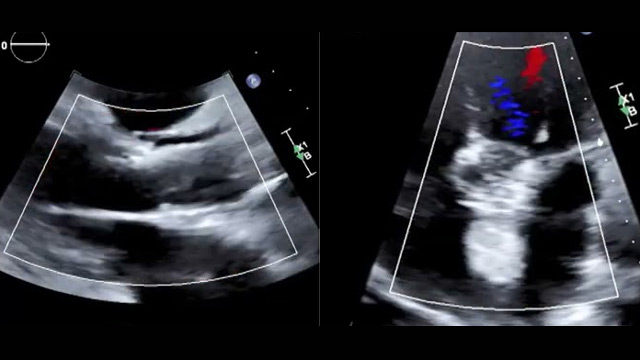

This session focuses on the critical role of intracoronary imaging in acute coronary syndrome (ACS) management. Topics include spontaneous coronary artery dissection (SCAD) cases, the utilization of IVUS and cardiac CT in emergent PCI during cardiogenic shock, and the assessment of non-culprit lesions using OCT to...